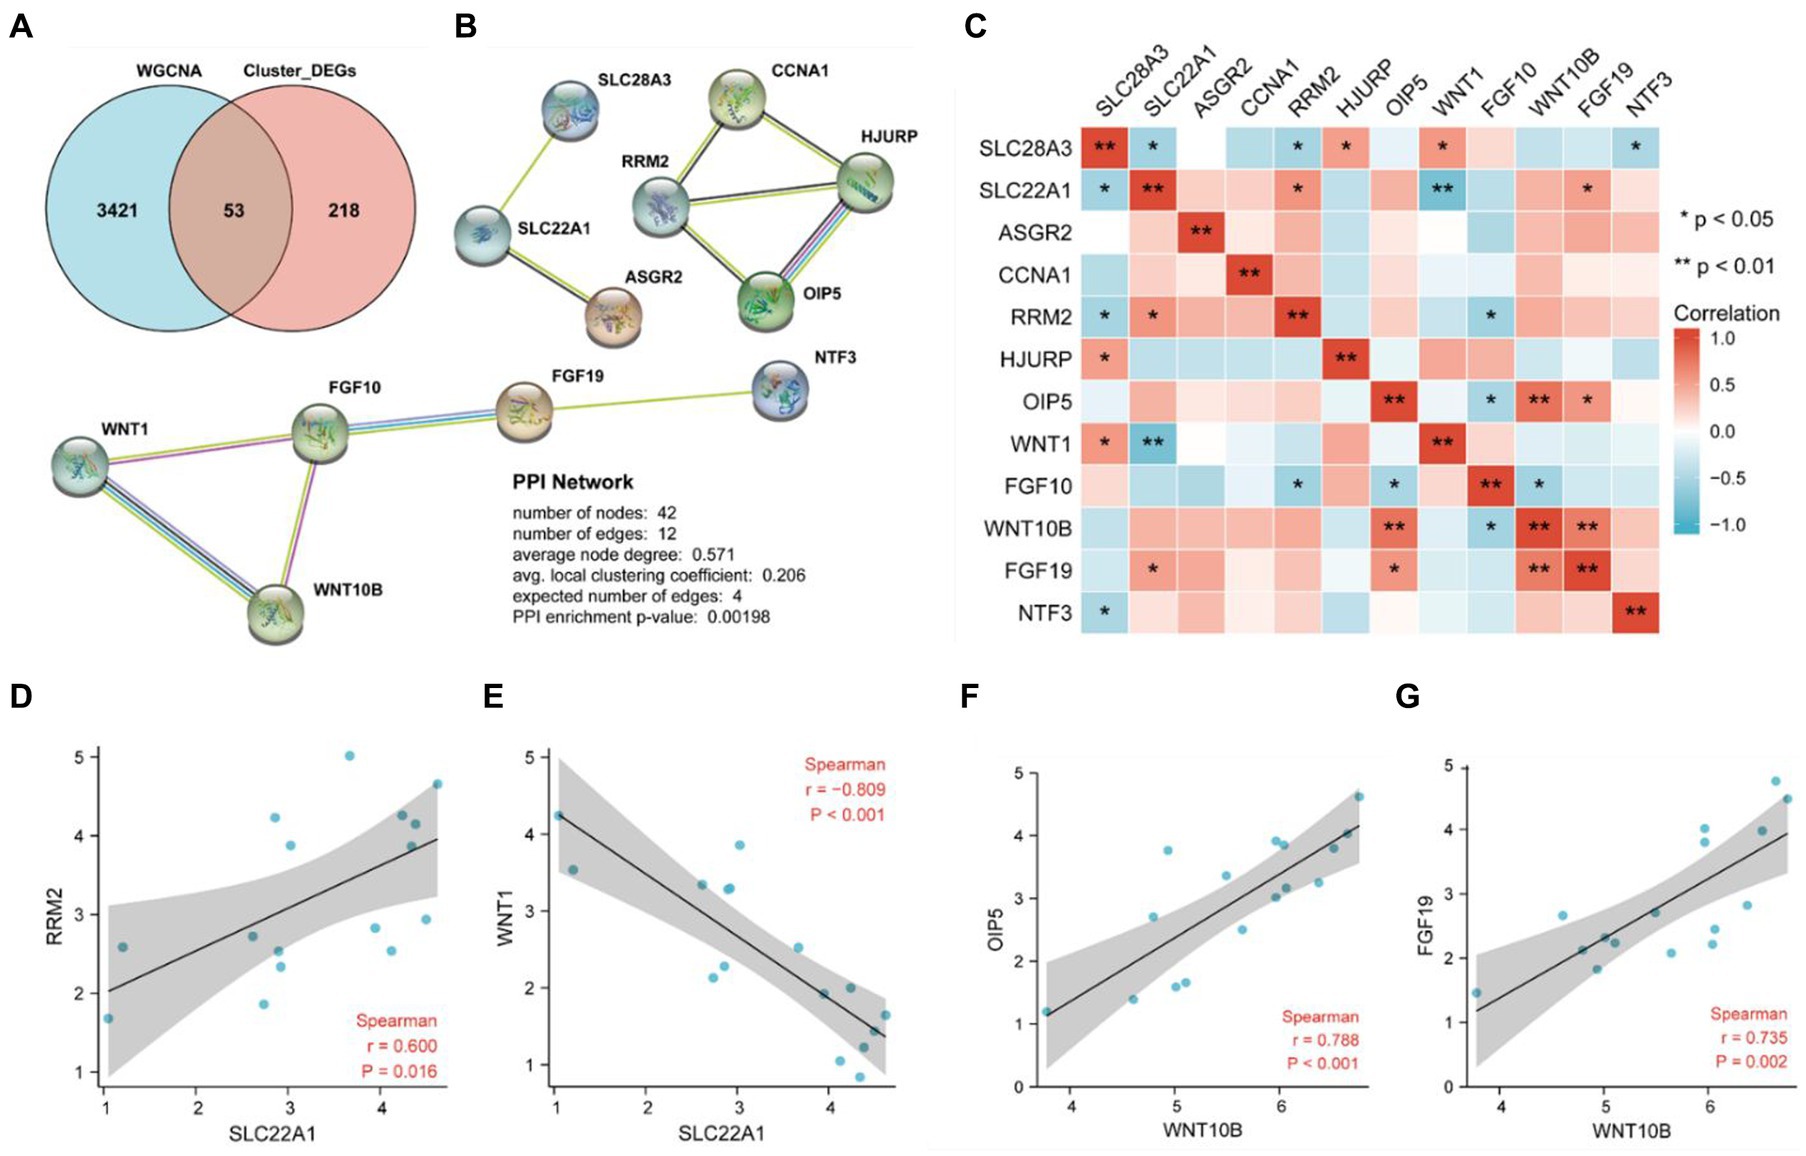

Frontiers in Parkinson Disease 2015年8月号(Vol.8 No.3。Optimal DaTQUANT Thresholds for Diagnostic Accuracy of。Frontiers | Identification of necroptosis-related genes in。